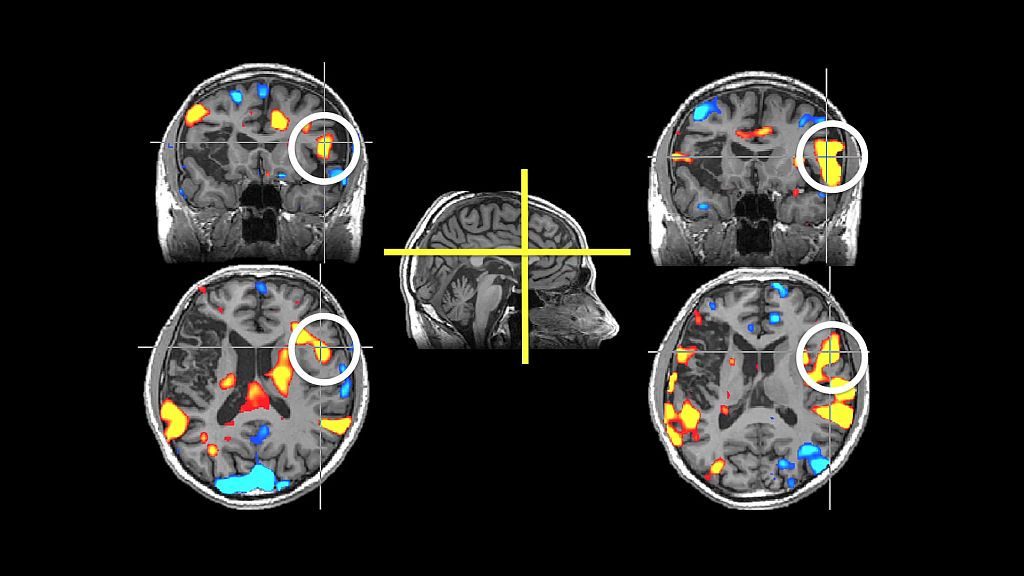

Early assessment will likely include a number of diagnostic tests and scans. The purpose of these tests is to establish a diagnosis of stroke and which type, and tailor treatment based on this.